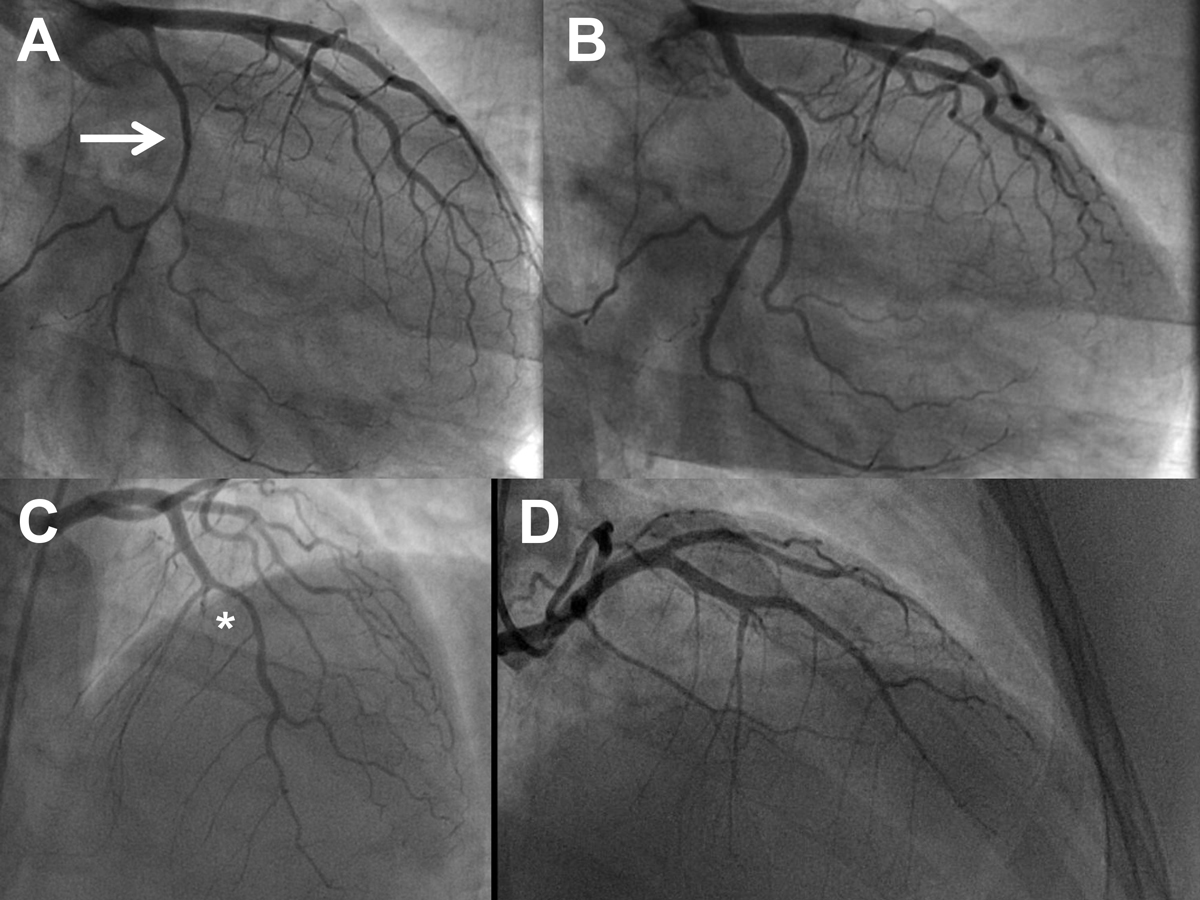

Figure 5 Serial angiogram of a 39-year-old woman with spontaneous coronary artery dissection (SCAD) on the entire left circumflex artery (LCX; panel A, right anterior oblique 35° view, arrow) and complete healing of the dissection at the repeat angiogram after 6 months (panel B, same view). Panel C: SCAD of the left anterior descending artery (LAD; asterisk) and the first diagonal branch 7.9 years later. Panel D: repeat angiogram 6 months later after conservative therapy showing healing of the dissections (cranial/right anterior oblique view) (see also table 4).